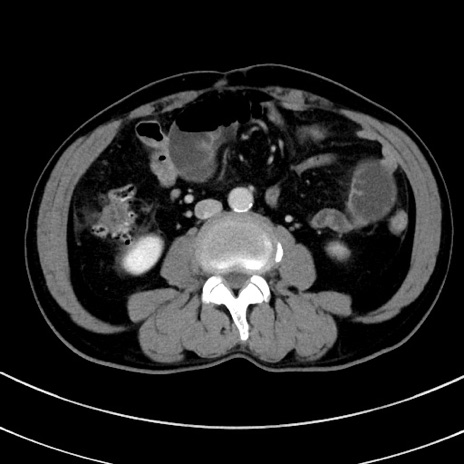

症例8(横断像)

【症例】 60歳代男性

【主訴】 黒色吐物

【現病歴】 4日前から嘔気自覚、2日前の朝食後にも嘔気あり、自分で手で嘔吐反射起こし嘔吐したところ血が混ざっていたため受診。

【既往歴】 5年前汎発性腹膜炎を伴う急性虫垂炎で手術、高血圧、前立腺肥大症、高脂血症

【身体所見】 腹部正中に手術癩痕あり 腹部平坦・軟圧痛なし膨満感あり

【データ】WBC 8400、CRP 4.54